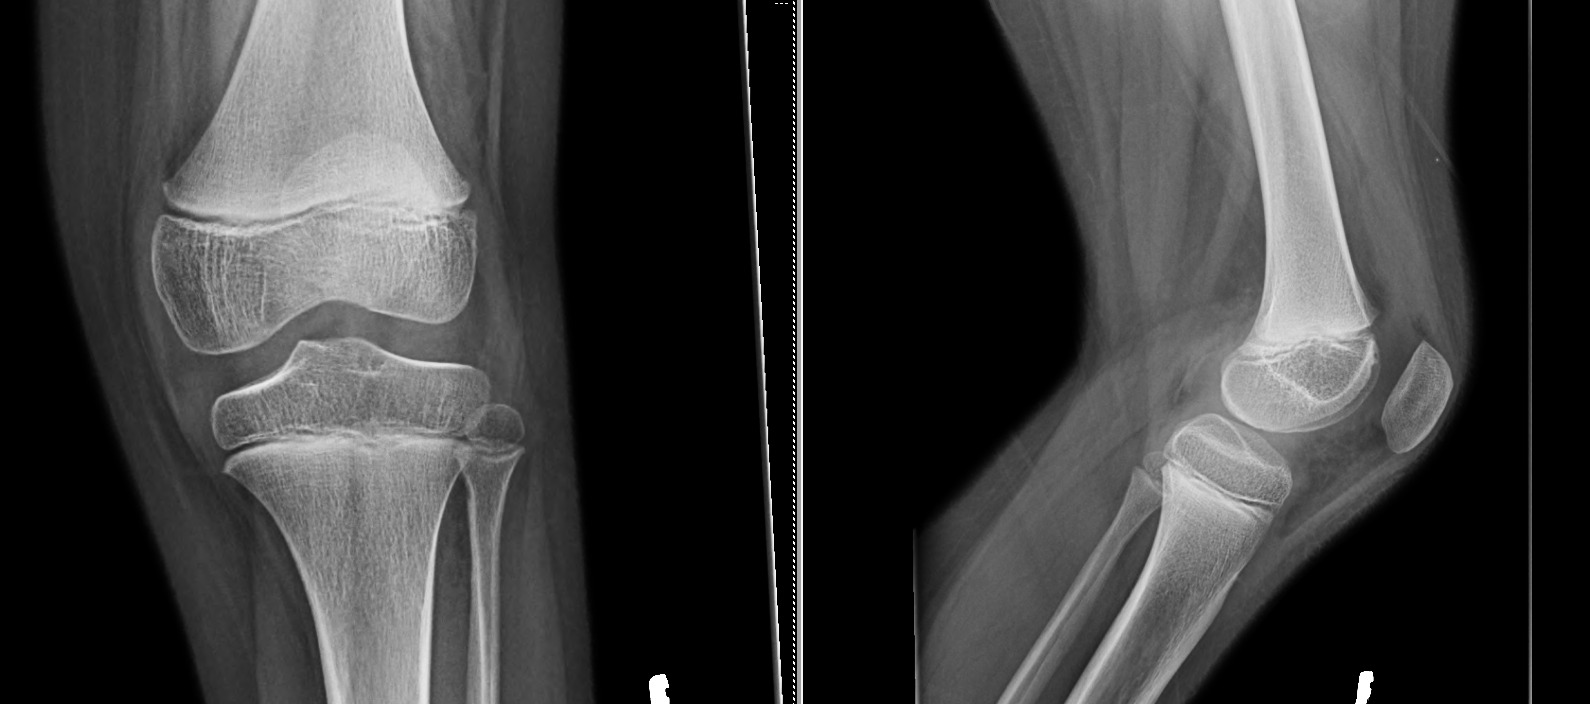

Physical examination of the patient’s left knee demonstrated passive range of motion that was 5 degrees shy of full extension with flexion to 130 degrees. She was 121 centimeters (3 feet 11 inches) tall and weighed 34 kilograms (74.8 lbs) with a BMI of 23.2. Her ligamentous knee exam was noted to be stable. She had tenderness over the lateral joint line and a sense fullness reported on the posterior aspect of her knee. Initial radiographs performed demonstrated normal anatomic alignment and did not reveal any bony hip or knee pathology (Figure 1).